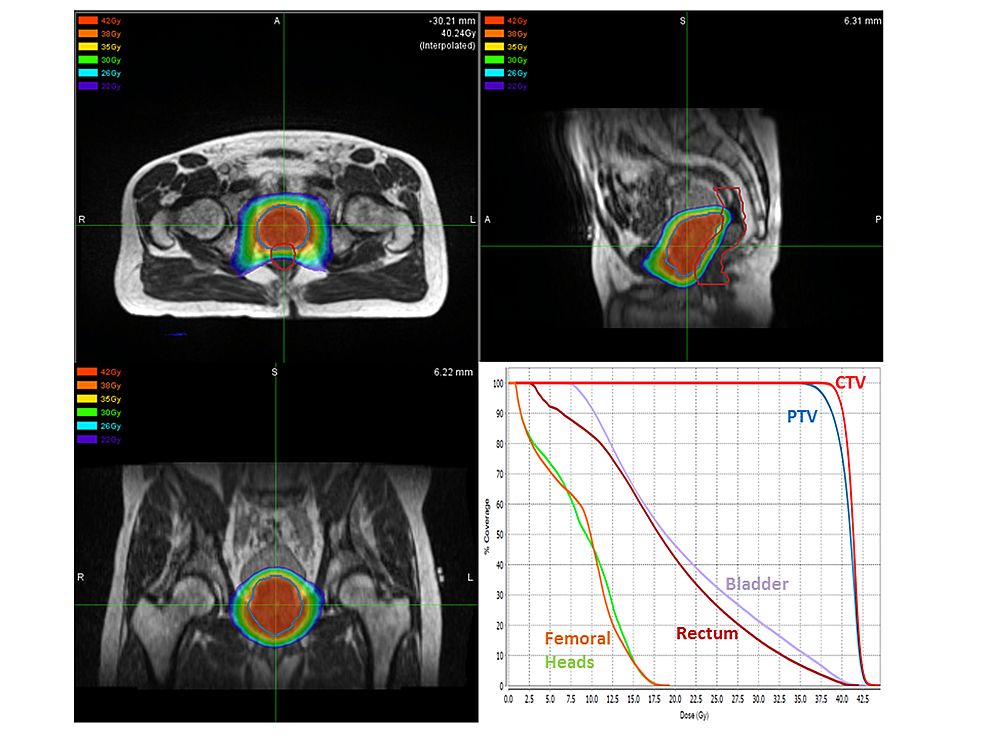

• Trattamenti Radioterapici: Studio e applicazione delle tecnologie più avanzate per colpire la malattia nel massimo rispetto dei tessuti sani.